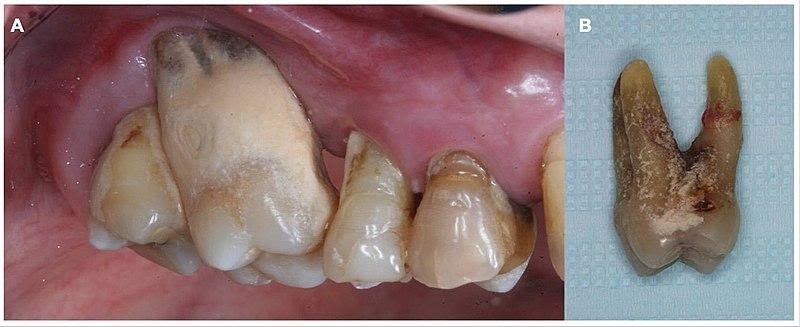

Тяжелый пародонтит. Обратите внимание, какое количество зубных отложений скололи с удаленного зуба.

Просто устранить бактерии недостаточно. Пародонтит в принципе необратим: сожранные связки уже никто не восстановит. У таких пациентов неизбежно будут возникать условия для повторного прикрепления бактерий и новых зубных бляшек. Поэтому при очень выраженных патологических десневых карманах мы проводим их кюретаж специальными инструментами. При этом как бы соскабливаются дно и стенки карманов, чтобы убрать остатки бактерий и обеспечить хорошие условия для дальнейшей пластики. После кюретажа хирург-пародонтолог проводит пластику дёсен. При этом частично или полностью восстанавливается эстетика. Мы стараемся убрать эффект обнажённых корней и чёрных провалов между зубами. В тяжёлой стадии полностью это устранить не получится.